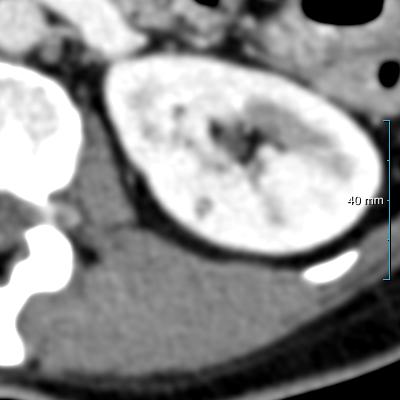

Refer to caption

(a) Input CT scan

(b) Annotations format 1

(c) Annotations format 2

Figure 2: Example illustrating the different annotation formats. Each subfigure shows the same axial section, with overlays depicting the annotations: (a) shows the axial CT section. (b) shows the annotations in format 1: parenchyma and kidney abnormalities as a single structure (yellow overlay). (c) shows the annotations in format 2: parenchyma (yellow overlay) and kidney abnormalities (red overlay) as different structures. All images have a window center of 60 HU and a window width of 360 HU.

This study utilized two annotation formats, format 1 and format 2, to store the annotations. Format 1 considers the kidney parenchyma and kidney abnormalities as a single class (see Figure 2(b)) while format 2 separates them into two classes (see Figure 2(c)).